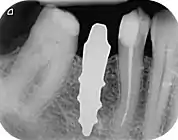

- 1 2 3 Pirker, W; Wiedemann, D; Lidauer, A; Kocher, A (2011). "Immediate, single stage, truly anatomic zirconia implant in lower molar replacement: a case report with 2.5 years follow-up". International Journal of Oral and Maxillofacial Surgery. 40 (2): 212–6. doi:10.1016/j.ijom.2010.08.003. PMID 20833511.